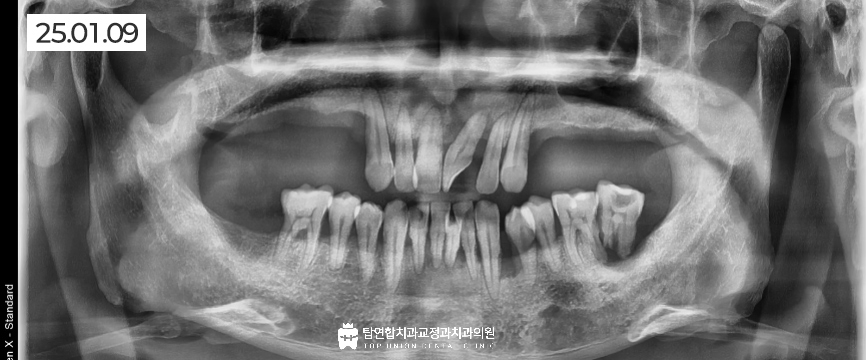

정확한 상태 확인을 위해서 전체 파노라마 x-ray를 촬영해 보았습니다.

이미 구강 내를 육안으로 확인하면서 예상했던 대로

치아의 주변 치조골이 거의 상실되어서

겨우 매달려있는 수준의 상태임이 확인되었습니다.

이미 거의 치조골을 벗어나서 기능을 못하고

치조골의 단단한 지지가 거의 상실된

위의 앞니 두 개는 발치하기로 하였습니다.

임플란트를 식립하기에도 치조골의

상태가 좋지 못했기 때문에

주변의 치아를 지지대 삼아서

연결하는 브릿지를 계획하였습니다.